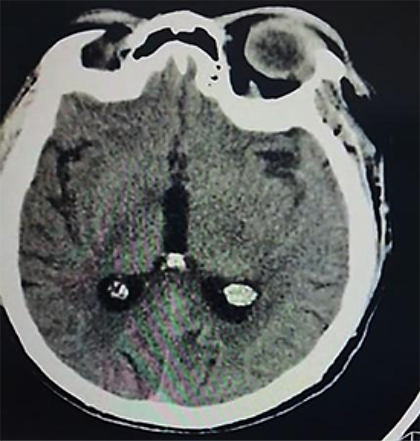

Ingresa con los diagnósticos de: accidente cerebrovascular hemorrágico (peri-troncal); Crisis hipertensiva tipo emergencia; hiponatremia hipotónica hipervolemica; enfermedad renal crónica KDIGO 5 en hemodiálisis; diabetes mellitus tipo 2 mal controlada e hipertensión arterial sistémica. Permaneció bajo monitorización continua de la presión arterial, asociado a vasodilatadores endovenosos (nitroprusiato de sodio 3-5 ug/k/min), seguimiento por el servicio de nefrodialisis, para continuar terapia de reemplazo renal; por otro lado fue evaluado por el servicio de neurocirugía quien indico por el momento tratamiento médico, asociado a medidas de protección cerebral; además fue evaluado por el servicio de cardiología, solicitando una ecocardiograma transtorácico: Hipertrofia concéntrica del ventrículo izquierdo, motilidad regional preservada, fracción de eyección de ventrículo izquierdo (FEVI) 66%; se realizó una Rx de tórax PA que mostro leve redistribución vascular pulmonar, catéter venoso central in situ; por otro lado en fecha 24/05/23 se realiza una angio resonancia magnética de cerebro que muestra hemorragia subaracnoidea y sangre en area prepontina, premedular y peripeduncular, además de cisuras frontoparietooccipitales, dilatación de tercer ventrículo, enfermedad vascular tipo microangiopatia (Figura 2a, b).